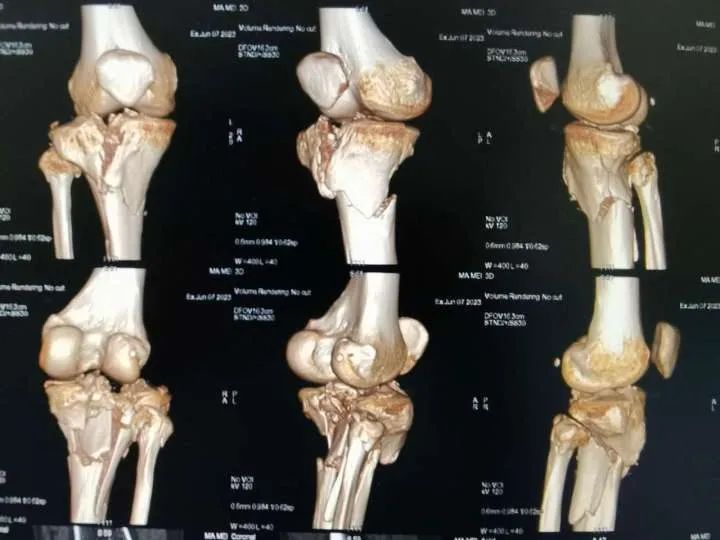

近期, 家住西乡县杨河镇的马女士骑着单车不慎重重摔倒,当即出现右膝关节肿胀、疼痛,腿无法再动弹,随后被送到西乡县中医医院。经急诊科检查诊断为“右胫骨近端粉碎性骨折合并膝关节脱位”,随即马女士入住骨三科。当班医生刘勇接诊后发现患者右膝部肿胀明显,疼痛拒按,关节极度屈曲,不能伸直,外形畸形,触摸足背动脉较健侧明显减弱。结合X线片检查,刘医生告知患者及家属,可以先复位固定纠正膝关节脱位,解除断骨对神经及血管的压迫。手法复位是西乡县中医院骨伤科传统技艺,多年来代代相授、传承改进,已形成中医院骨伤科独特的优势技术。马女士受伤后第一时间来到中医院,也算是慕名而来。随后刘勇医生和董兵医生密切配合,为患者先行脱位手法复位并石膏外固定制动,复位后马女士立即感觉右膝疼痛明显缓解!

为了尽量缩短马女士康复时间,科主任孙明军组织科内会诊,经过反复分析和调整,为患者制定了详细、周密、个性化的治疗方案。先以局部针刺减压,并抗炎、消肿止痛、补液、对症治疗症状缓解后,再采取胫骨近端内外侧锁定板固定手术(右胫骨近端粉碎性骨折切腹内固定术+同种异体骨植骨术+膝关节腔清理术)。

粉碎性骨折和膝关节脱位到底有多严重?

粉碎性骨折是一种骨折类型,其特点是骨折端的骨组织在受伤时被压碎成多个碎片。这种骨折常见于高速交通事故、高坠落、重型碾压等严重外力作用下。由于骨折端的骨组织碎片较多且不稳定,这类骨折常伴随有明显的疼痛、肿胀、变形和活动受限等严重症状。粉碎性骨折需要经过专业的治疗和严密的监护,通常会进行手术切复内固定或异体植骨等复杂手术,以稳固骨折端并促进骨折的愈合。

膝关节脱位是指膝关节内髁和外髁的关节面完全脱离,使得膝关节处于不正常的位置。这种情况通常由剧烈的外力作用引起,例如运动损伤、车祸或跌倒等。膝关节脱位严重影响患者的行走和活动能力,会出现严重的关节疼痛、肿胀、变形和不能正常活动等症状。治疗膝关节脱位需要及时复位,并进行综合治疗,如康复锻炼和康复理疗,以恢复关节功能。